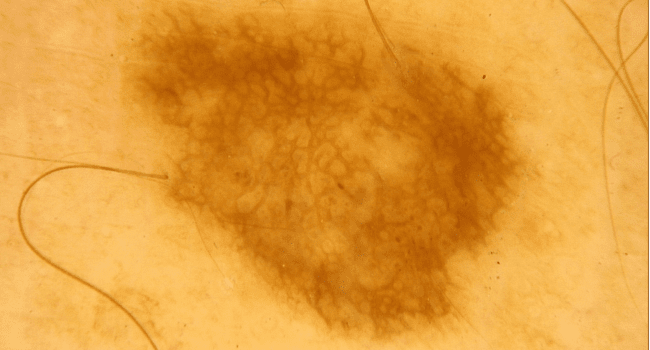

Czerniak złośliwy

Niestety część znamion pod wpływem różnych czynników rakotwórczych (kancerogennych) może przekształcić się w czerniaka skóry. To jeden z najbardziej niebezpiecznych i złośliwych nowotworów. Jego wczesne wykrycie znacznie jednak poprawia rokowania, czerniak wykryty we wczesnym stadium jest praktycznie 100% wyleczalny.

Jak wygląda czerniak?

Dla profilaktyki raków skóry i czerniaka istotna jest samoobserwacja znamion występujących na powierzchni całego ciała. Jak odróżnić pieprzyk od czerniaka? Jakie zmiany powinny wzbudzić zainteresowanie? Kiedy udać się do lekarza?

Dla pacjentów najprostszym sposobem różnicowania pieprzyków jest posługiwanie się kryteriami ABCDE (angielski akronim Asymetry, Border, Color, Diameter, Evolution), które zostały stworzone na Uniwersytecie Nowy Jork 35 lat temu. Kryteria te miały być prostym narzędziem w codziennej praktyce, łatwym do zapamiętania, wzbudzającym czujność zarówno pacjentów jak i lekarzy na cechy kliniczne wczesnego czerniaka. Tak się też stało.

Obejrzyj film i poznaj metodę ABCDE na Instagramie

Opierając się na własnym doświadczeniu w ocenie chorych, członkowie New York University School of Medicine Melanoma Cooperative Group stwierdzili, że asymetria wczesnej postaci czerniaka, nieregularność jej brzegów oraz różnorodność barw były ściśle związane z przekraczaniem przez nią średnicy 6 mm. Co nie zmienia faktu, że ta metoda pozwala wykryć i zróżnicować nieco mniejsze i wcześniejsze pod względem zaawansowania postaci czerniaka.

Reasumując każdy pieprzyk o asymetrycznych kształtach, nierównych brzegach, zmieniający kolor i/lub średnicę, nabrzmiały, podrażniony, krwawiący wymaga natychmiastowej konsultacji z lekarzem specjalistą i wykonania badania dermatoskopowego.

Nie ma jednego wzorca czerniaka dlatego różnicowanie ze zwykłymi znamionami bywa trudne nawet dla specjalistów w tej dziedzinie. W diagnostyce dermatologicznej do każdego przypadku podchodzi się indywidualnie.

Niestety znamiona mogą do złudzenia przypominać czerniaki, więc odróżnienie zwykłego pieprzyka od typowego czerniaka może być trudne. Znamiona atypowe – dysplastyczne mogą imitować czerniaki, a niektóre czerniaki bardzo przypominają znamiona i dopiero usunięcie zmiany i badanie histopatologiczne pozwalają na postawienie trafnej diagnozy.

Porównaj zestawienie zdjęć zwykłych znamion i czerniaka i zobacz ich możliwe podobieństwo!